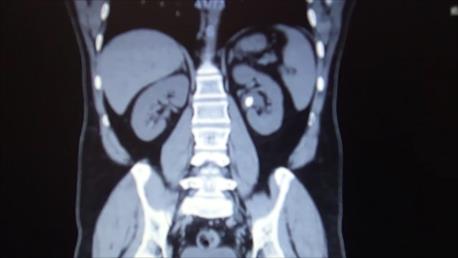

Teknolojinin ilerlemesi ile birlikte böbrek taşlarının tedavisinde birçok alternatif tedavi seçenekleri ortaya çıkmıştır. Böbrek taşlarının tedavisinde asıl amaç böbreğe en az zarar vererek maksimum taşsızlık sağlamaktır. Geçmişte açık cerrahi ile tedavi edilen böbrek taşları son yıllarda gelişen teknoloji paralel olarak Perkütan nefrolitotomi (PCNL), Retrograd İntrarenal cerrahi (RIRS) yada vücut dışından şok dalgaları ile taş kırma (ESWL) tedavisi gibi birçok alternatif metodla tedavi edilmektedir.

Yeni nesil fleksibl üreteroskopların ve holmium lazer gibi etkin ve güvenli taş kırıcıların geliştirilmesi ile Retrograd İntrarenal cerrahi (RIRS) taş tedavisinde önemli bir alternatif haline gelmiştir. Günümüzde açık cerrahiye, perkütan nefrolitotomiye (PCNL) gereksinim duyulmadan Retrograd İntrarenal cerrahi (RIRS) ile başarılı bir şekilde tedavi edilmektedir.